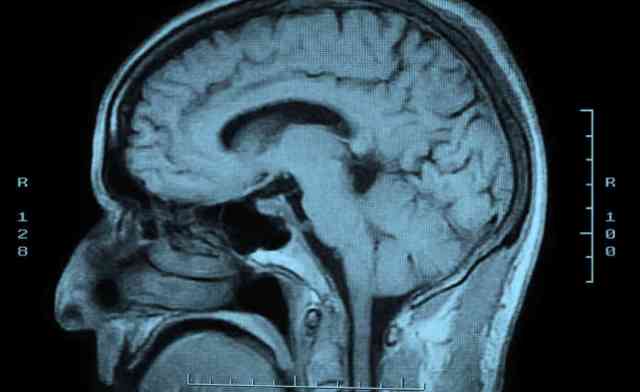

“She understands everything I say,” he would say. ” She tells me things.” The woman was unresponsive – no eye opening, no movement, and certainly no talking – for months. We had had many family meetings and at one of them, when presented with the grave prognosis yet again, Alex exclaimed: “What about a brain transplant?” This seemed to me an example of how unreasonable patient expectations can sometimes be. But then I Googled it and saw you could get a brain transplant $500,000: they would transplant your brain into a better body.

Trying to bridge that gap is difficult for the child who is witness to the parent’s suffering, much as it is for the doctors at whose hands the parent is suffering. It is impossible to capture what being critically ill looks like, impossible to tell others who haven’t seen it for themselves. Impossible to explain what it feels like to walk in and see the person you love, this actual human being who raised you, who held your hand, who said things to you, to see this person not as themselves. It is impossible to bear seeing the tubes and catheters penetrating virtually every orifice, seeing that they don’t respond to your voice, they don’t open their eyes, they don’t recognize who you are. We feel so invincible when we are young, but in sickness, we are, none of us, all that different. It is impossible to see this person, who in your head is still alive and truly themselves, now so close to death that it is obvious the road back to you is far less likely than the road forward.

It is a picture that all the improbable statistics fail to convey. Your loved one will most likely die, yes. But why not play the odds – even a 1% chance might be worth a roll of the dice. What we fail to communicate, what people fail to see too often until they witness the violations of their loved ones at our hands, is that there are things worse than death. Walking in an intensive care unit and seeing a loved one who is likely to spend however little time is left shuffled between various acute and chronic care units, for many, is a fate worse than death.